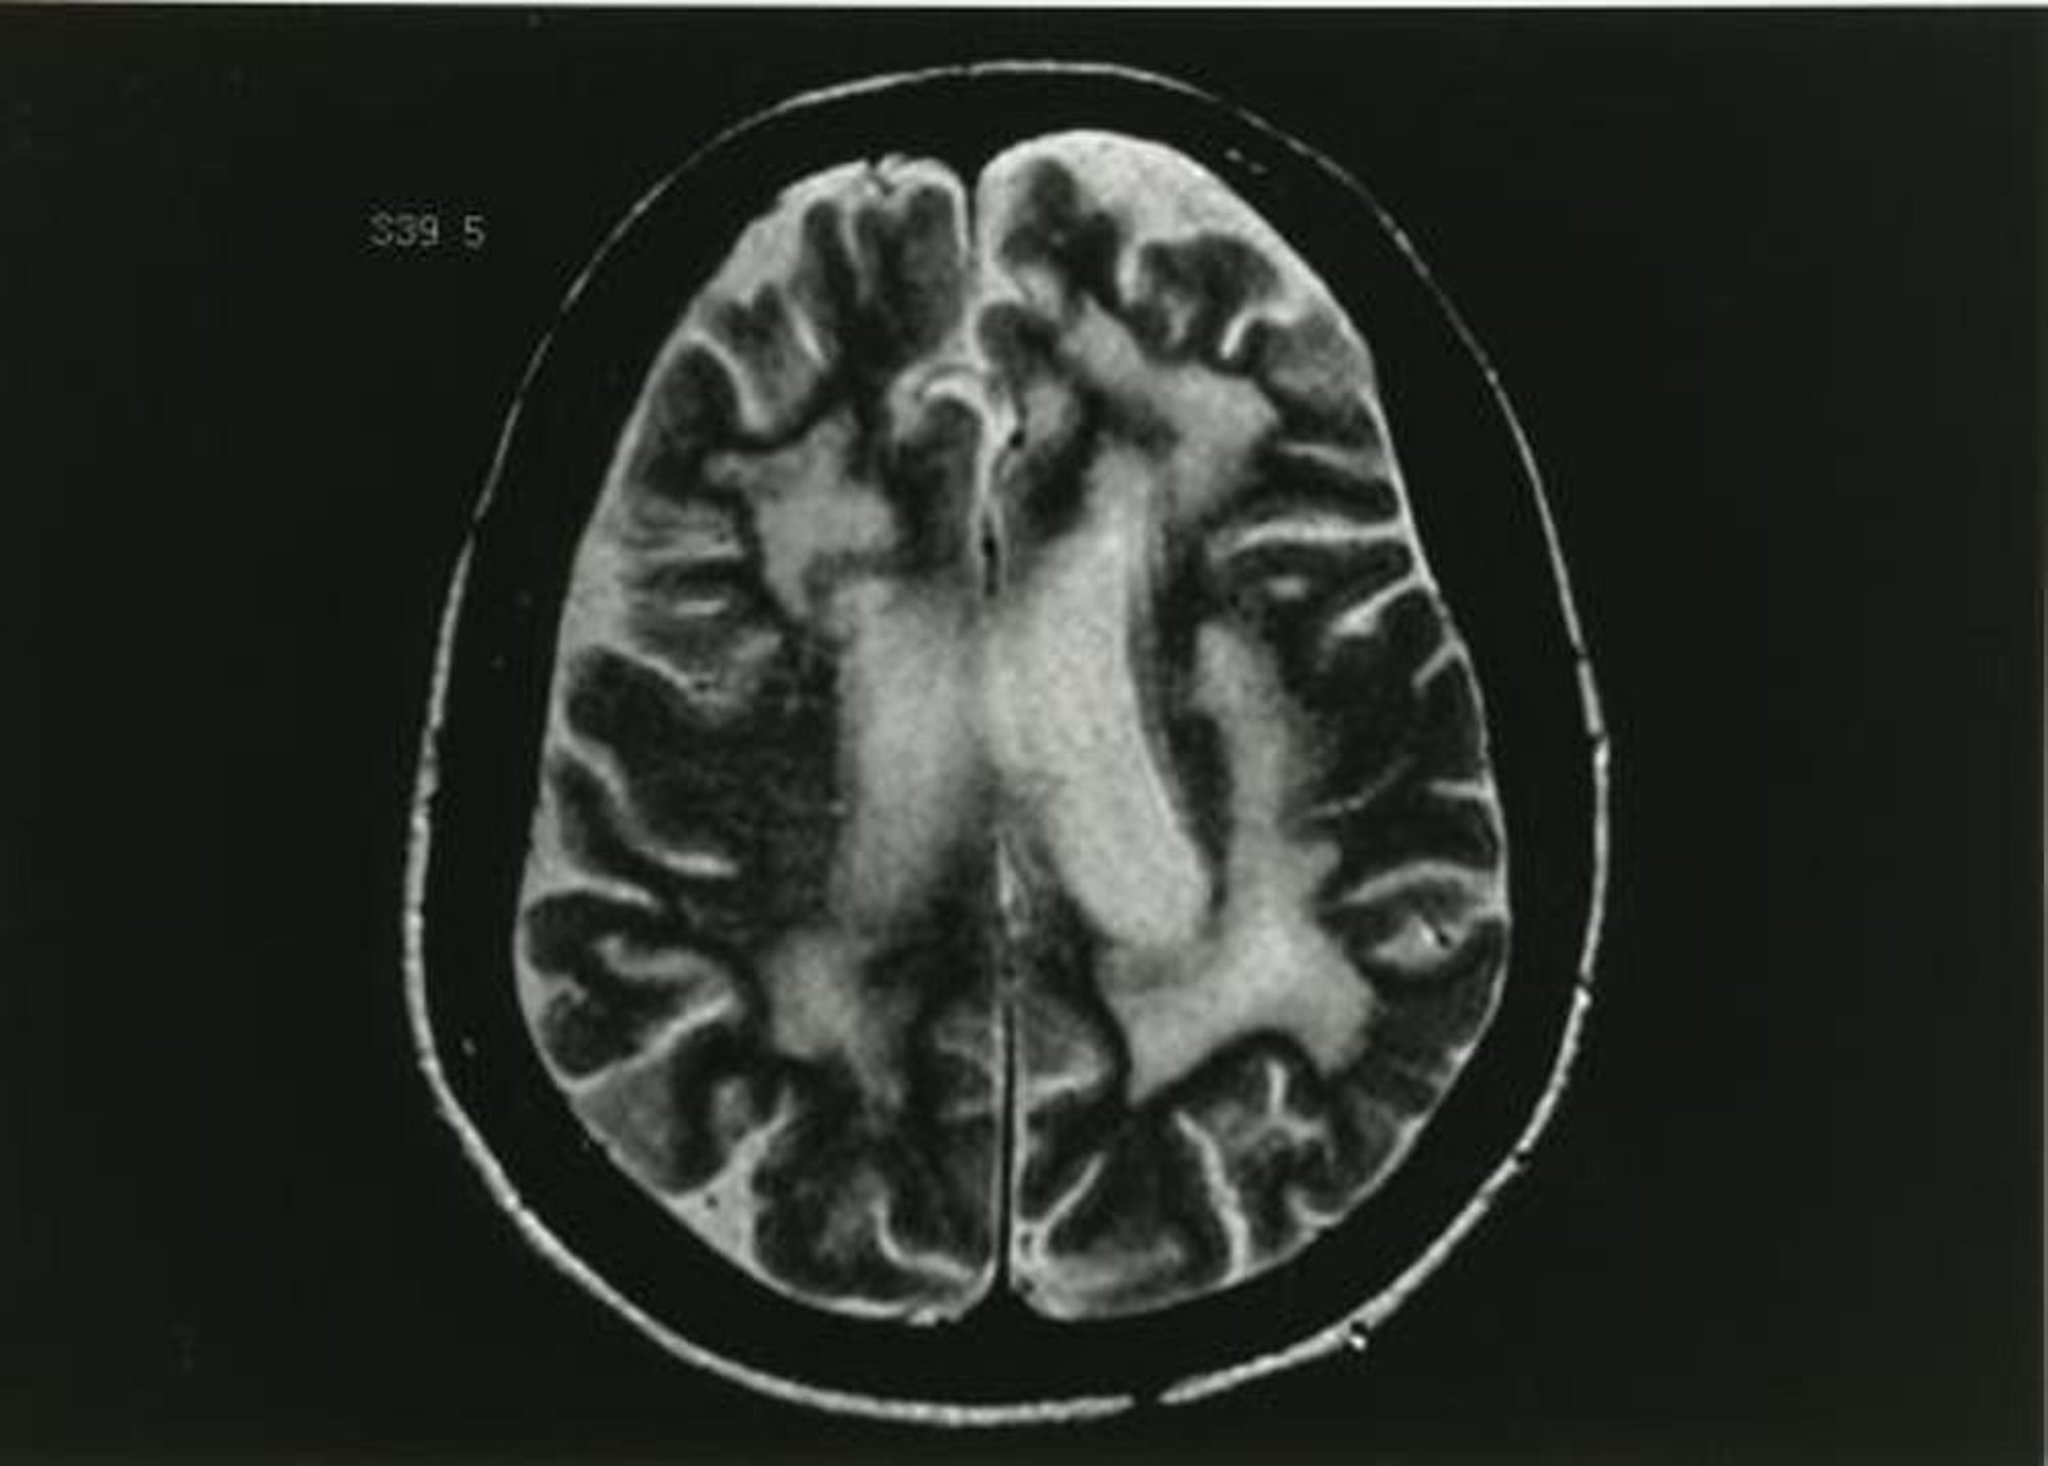

進行性多巣性白質脳症

このMRI T2強調像には,多発性の白質病変が示されている。

Image provided by John E.Greenlee, MD.